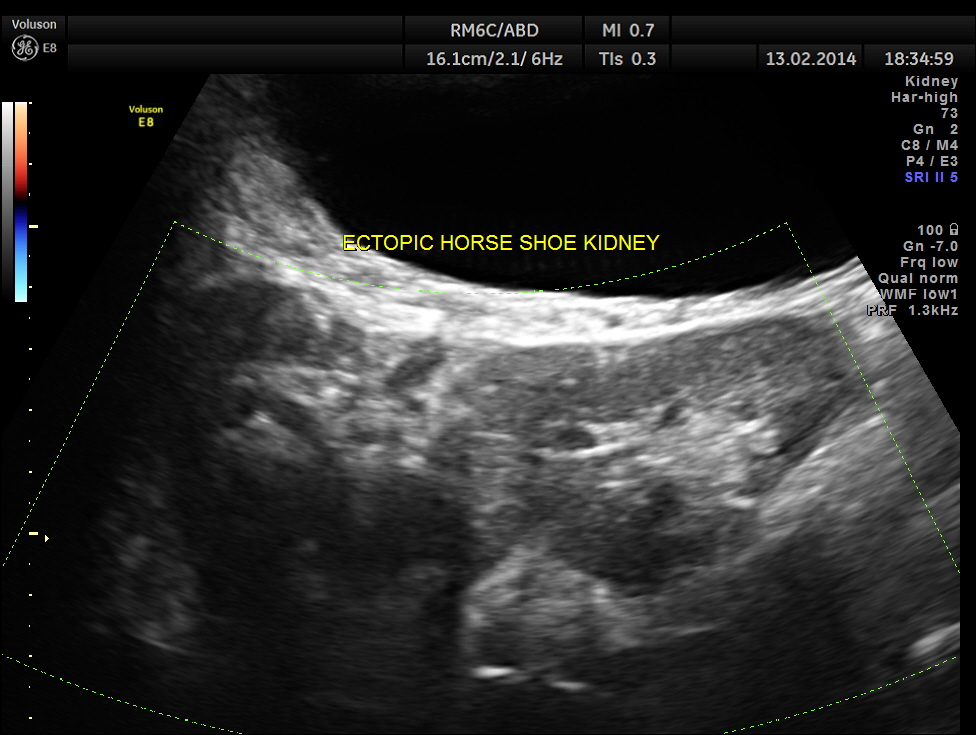

The following are the pictures of the kidney , which show the congenital horse shoe kidneys , placed ectopically in the pelvis. He had no urinary symptoms or low back ache at any time .

The right and left portions of the horse shoe are shown separately below

The power doppler pictures are given below.